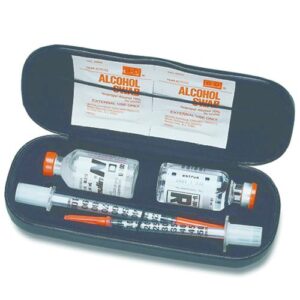

Diabetes Care